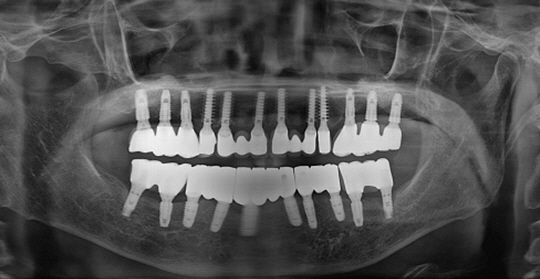

(38세 남 환자)